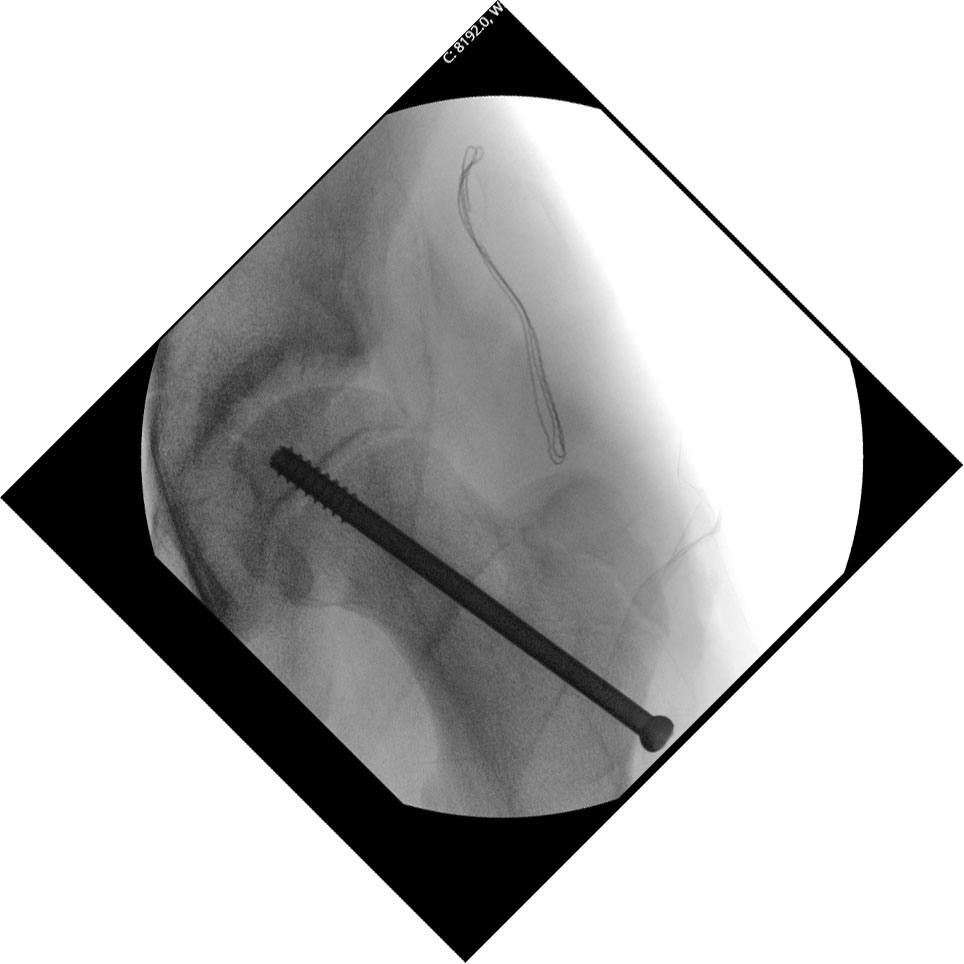

Poskliz glave bedrene kosti uvijek se liječi kirurški – stabilizacija/fiksacija pomaknute glave bedrene kosti vijkom, slika 2. Nakon operacije dijete treba hodati uz rasterećenje podlaktičnim štakama kroz 6 tjedana. Operaciju treba napraviti što prije moguće da se izbjegne što veći pomak glave. S većim pomakom glave bedrene kosti rastu šanse da se krvne žile koje vode do glave pokidaju, da se prekine opskrba krvlju glave bedrene kosti te da ona postepeno prijeđe u avaskularnu nekrozu – infarkt. To je teška posljedica poskliza glave bedrene kosti koja uzrokuje velike bolnosti i rješava se ugradnjom umjetnog zgloba kuka. Blaži stupnjevi poskliza glave bedrene kosti nakon operacije imaju dobru prognozu jer može doći do remodeliranja kosti u vratu tako da kuk poprima potpuno zdravi oblik. Nažalost, ponekad i nakon uspješno izvedene operacije kuk ostaje promijenjen i vremenom ima veću šansu za razvoj sekundarnog osteoartritisa – potrošnje zglobne hrskavice.

Slika 2.